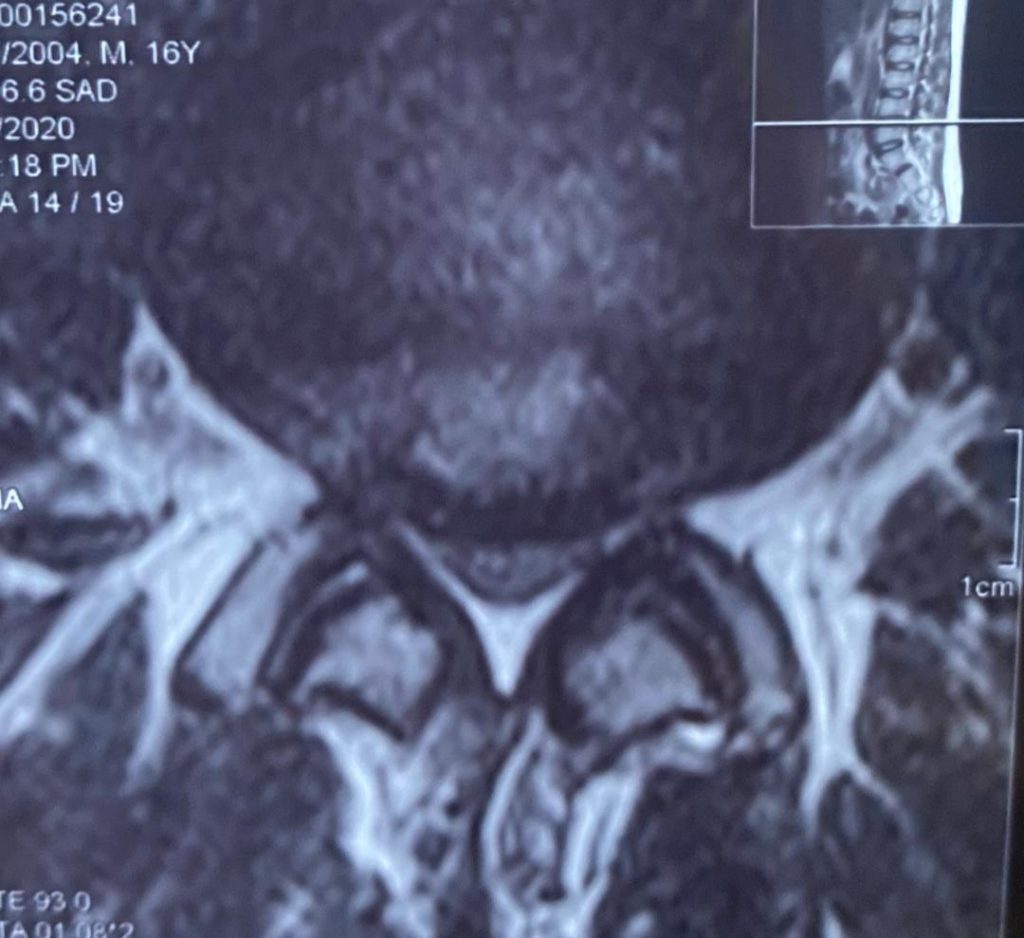

تصاویر قبل ار جراحی

پارگی دیسک و آسیب مفصل فاست L4-L5 وجود داشت که عمل جراحی میکروسکوپیک فنستراسیون و دیسککتومی دوطرفه انجام شد.